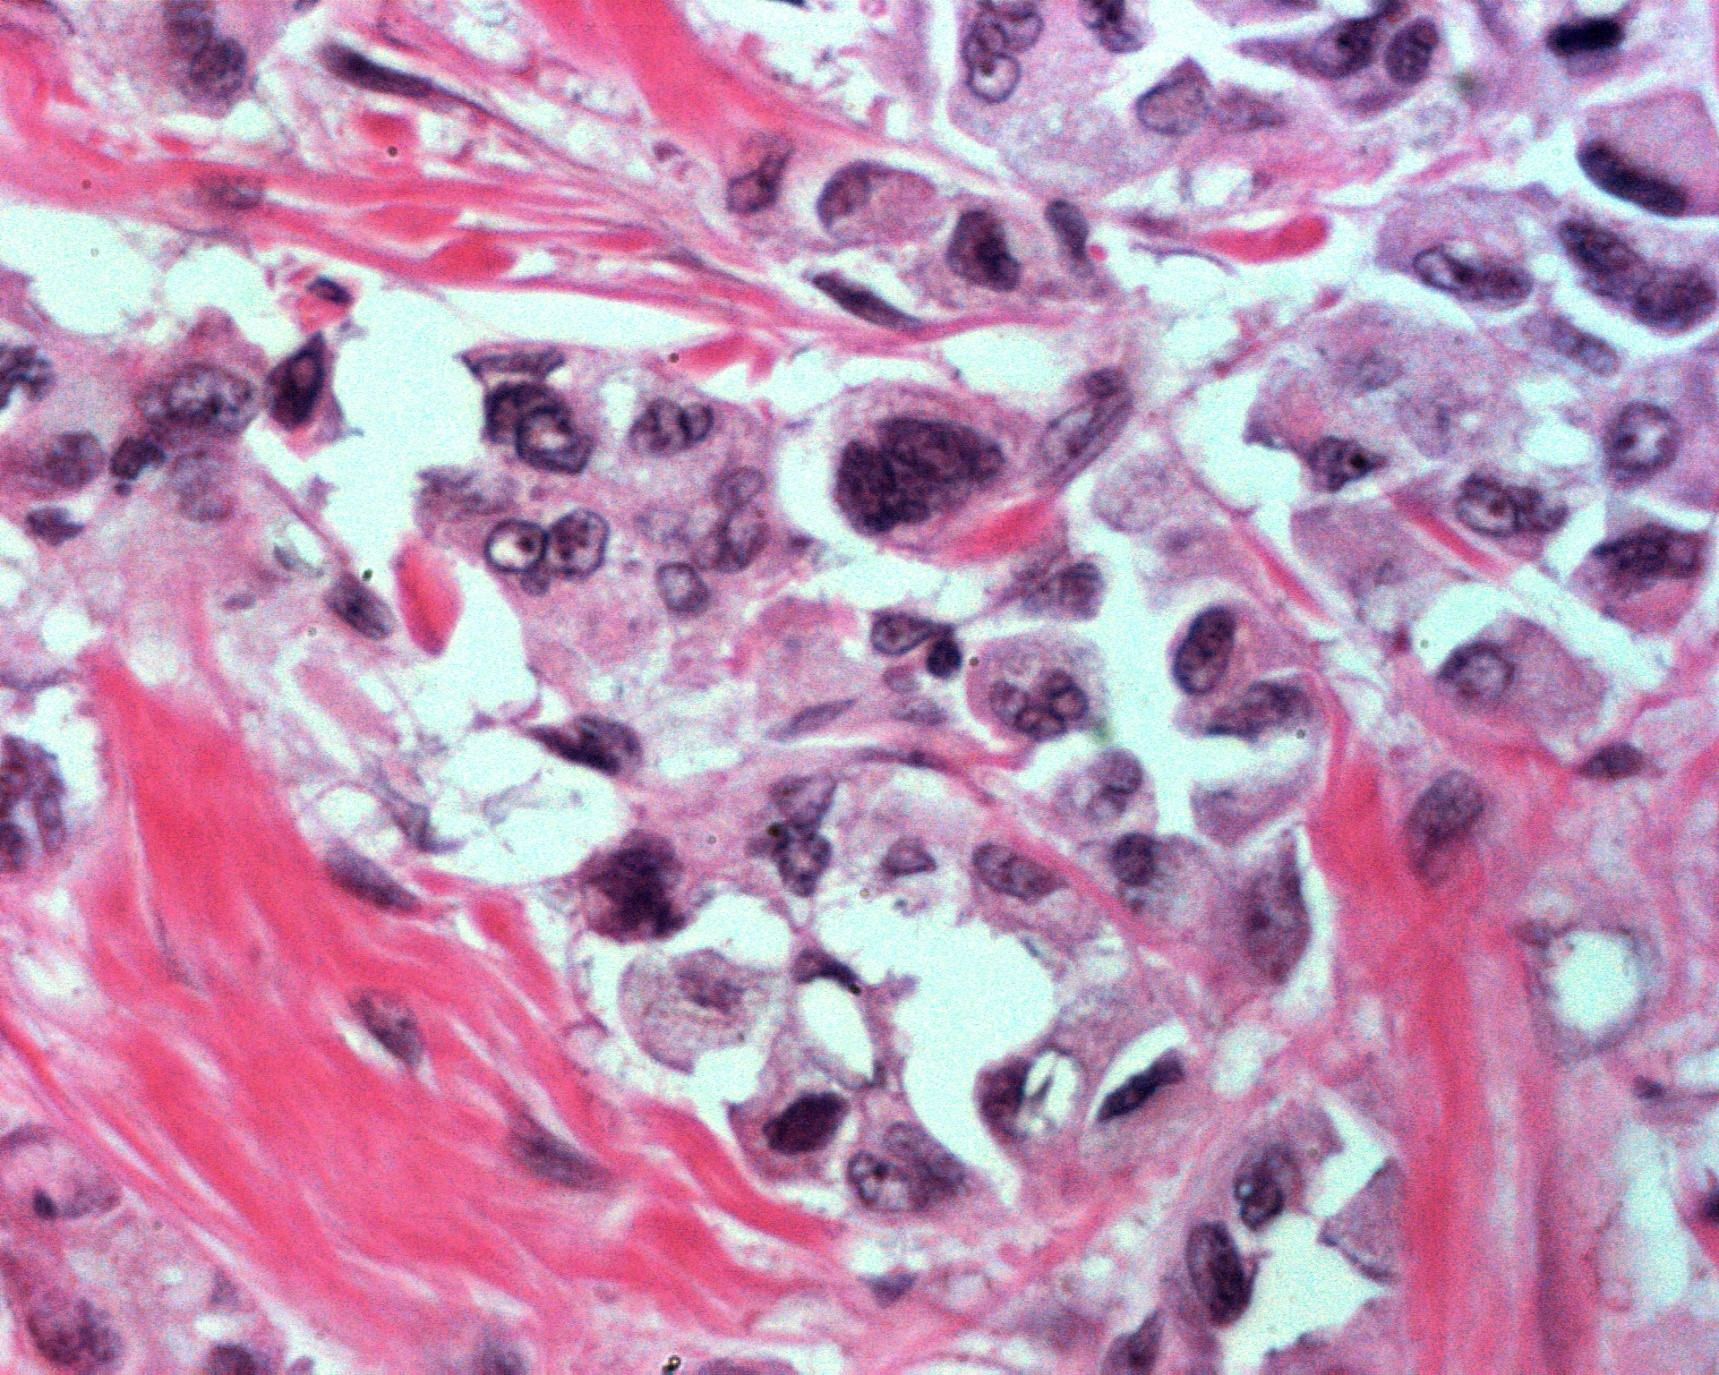

Imágenes microscópicas de la neoplasia en mama:

Carcinoma metaplásico productor de matriz o de tipo mixto, con respuesta categoría I de RCB o Miller y Payne 3.